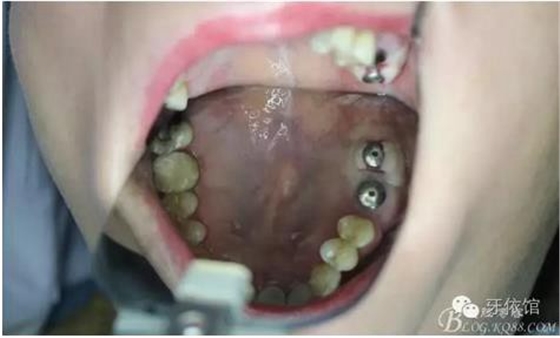

右上7上愈合基臺

三周后右下7

三周后右上6,7